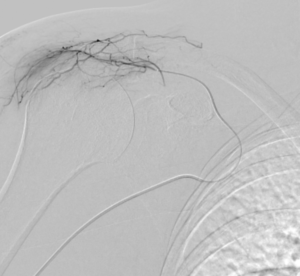

Grâce à l’imagerie de précision (angiographie), le radiologue interventionnel identifie ces vaisseaux « anormaux » et les occlut sélectivement. En bloquant leur flux sanguin, on réduit l’apport en oxygène et nutriments à la zone enflammée, favorisant une résolution rapide des symptômes.

- Guidage par imagerie : Le cathéter est avancé jusqu’à l’artère sous-clavière sous contrôle radioscopique en temps réel.

- Injection ciblée : Lipiodol dilué dans du produit de contraste iodé est injecté pour boucher les artères pathologiques.

- Vérification : Angiographie de contrôle pour confirmer le succès.